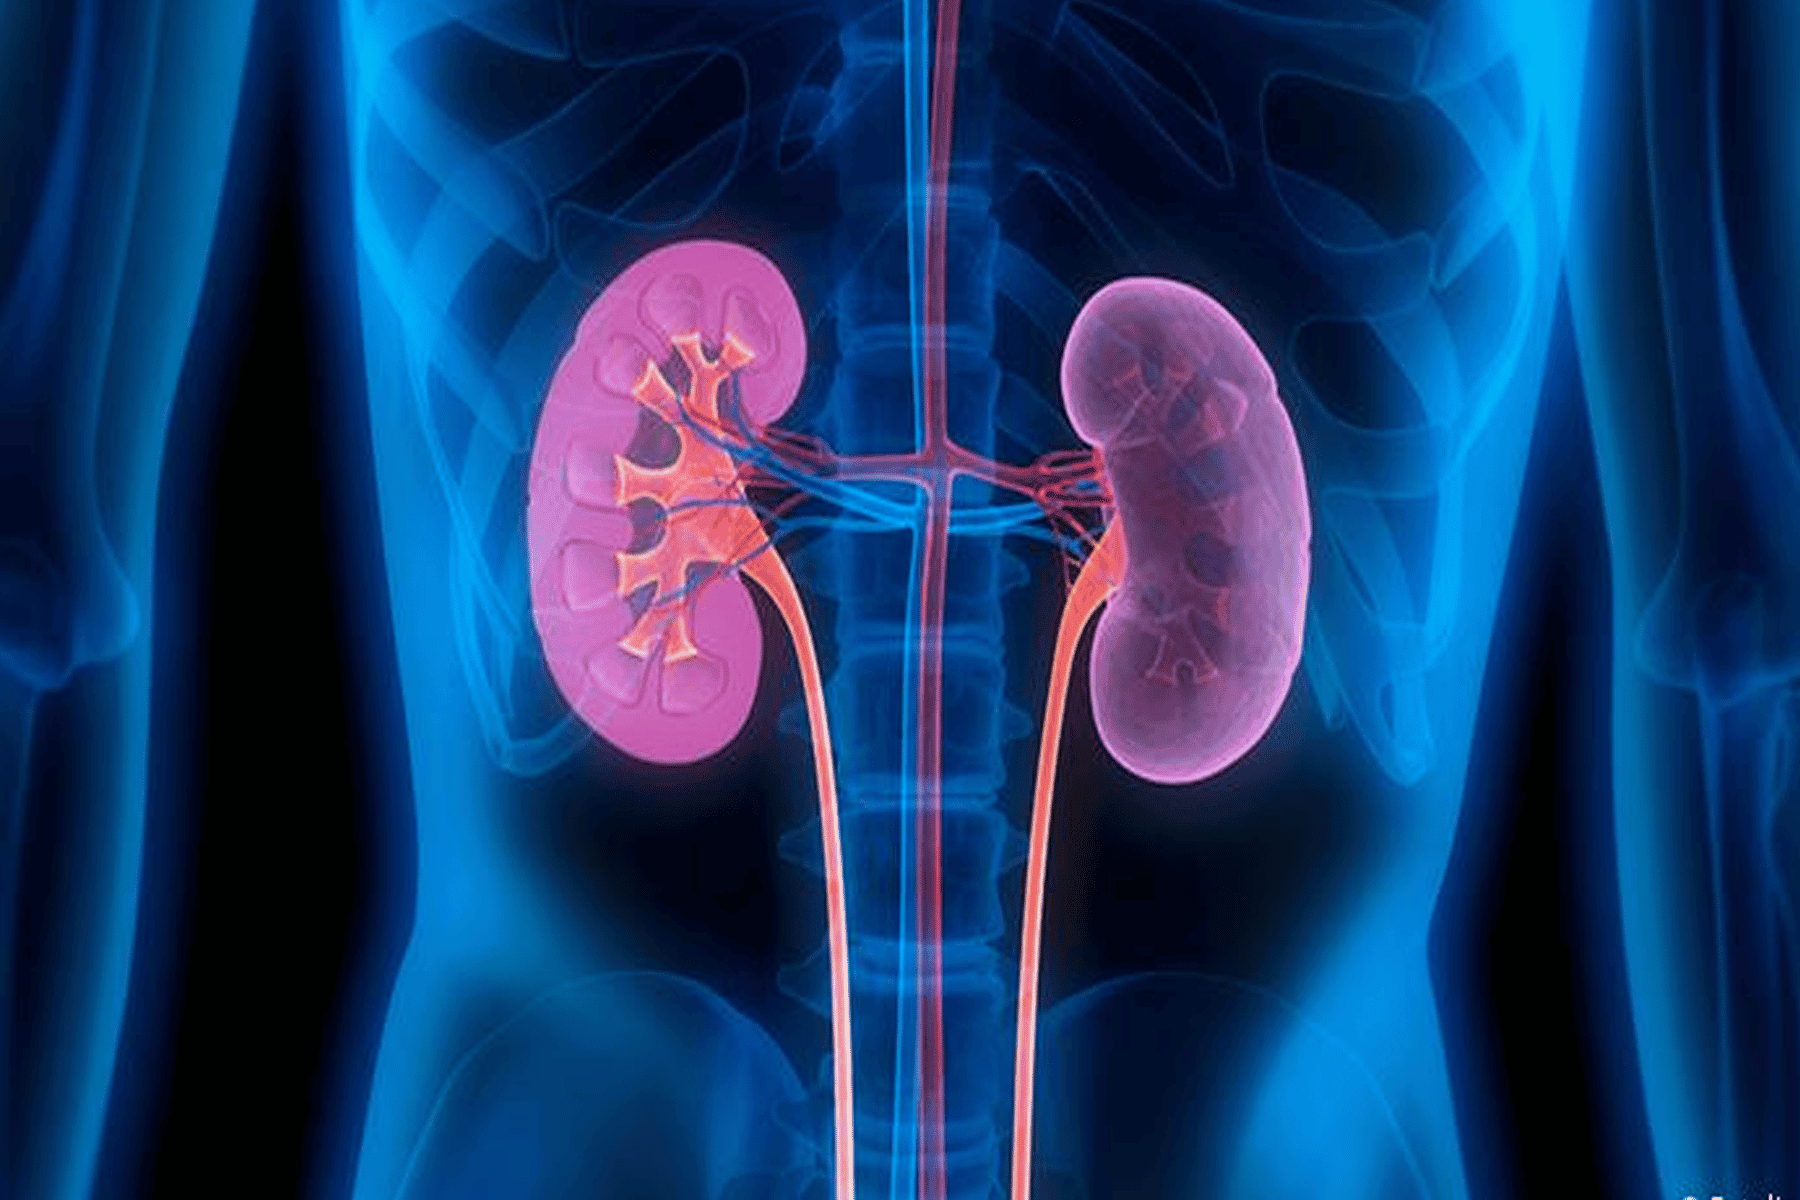

7 عادات تدّمر الكلى

وطن- عادة ما نقوم بالعديد من العادات السيئة التي تصبح ضمن يوميات حياتنا والتي غالباً ما تسبب العديد من الامراض من دون علمنا لا سيما في الكلى.

إليكم أبرز هذه العادات:

1/عدم شرب المياه: تعمل الكلى على تصفية الدم والتخلص من السموم والنفايات. عندما لا نشرب الماء بكميات كافية خلال النهار، فإن السموم تبدأ في التراكم ويمكن أن تسبب أضرارا بالغة في الجسم.

2/الملح في الطعام: إذا استهلكنا كميات كبيرة من الملح فإن ذلك سيؤدي إلى ارتفاع ضغط الدم وبالتالي يضع الكثير من الضغط على الكلى. لذلك ينصح بأن لا يزيد احتواء الطعام عن 5 غرامات من الملح يومياً.

7 عادات يومية تدمر الكلى من دون علمك.. فما هي؟

3/الدخول الى المرحاض: يتجاهل البعض الرغبة للذهاب الى المرحاض لأنهم مشغولون جداً أو يتجنبون الحمامات العامة. الاحتفاظ بالبول على أساس منتظم يزيد من ضغط البول ويمكن أن يؤدي إلى الفشل الكلوي، وحصى الكلى.

4/نقص الفيتامينات والمعادن: تناول الطعام المكون من الخضار والفواكه الطازجة المهمة لصحتك العامة ووظائف الكلى الجيدة. لأن النقص الكثير من فيتامين B6 والمغنيسيوم يزيد من مخاطر حصى الكلى أو الفشل الكلوي.

5/استهلاك كميات كبيرة من البروتين الحيواني: إن الإفراط في الاستهلاك من البروتين، وخصوصا اللحوم الحمراء، يزيد العبء على الكلى في التمثيل الغذائي، وهذا يمكن أن يؤدي إلى تلف الكلى أو خلل مع مرور الوقت.

6/النوم: يرتبط الحرمان من النوم المزمن بكثير من الأمراض وأمراض الكلى خاصة وذلك لأنه أثناء الليل أنسجة الكلى تقوم بإصلاح خلايا الجسم التالفة، حتى تعطي للجسم الوقت للشفاء وإصلاح نفسه.

7/إساءة استخدام مسكنات الألم: الكثير من الناس يتناولون المسكنات لآلام الصغيرة في حين أن هناك العديد من الحلول الطبيعية والعلاجات الآمنة المتاحة. الاستخدام المفرط أو تعاطي مسكن للألم يمكن أن يؤدي إلى تلف شديد في الكبد والكلى